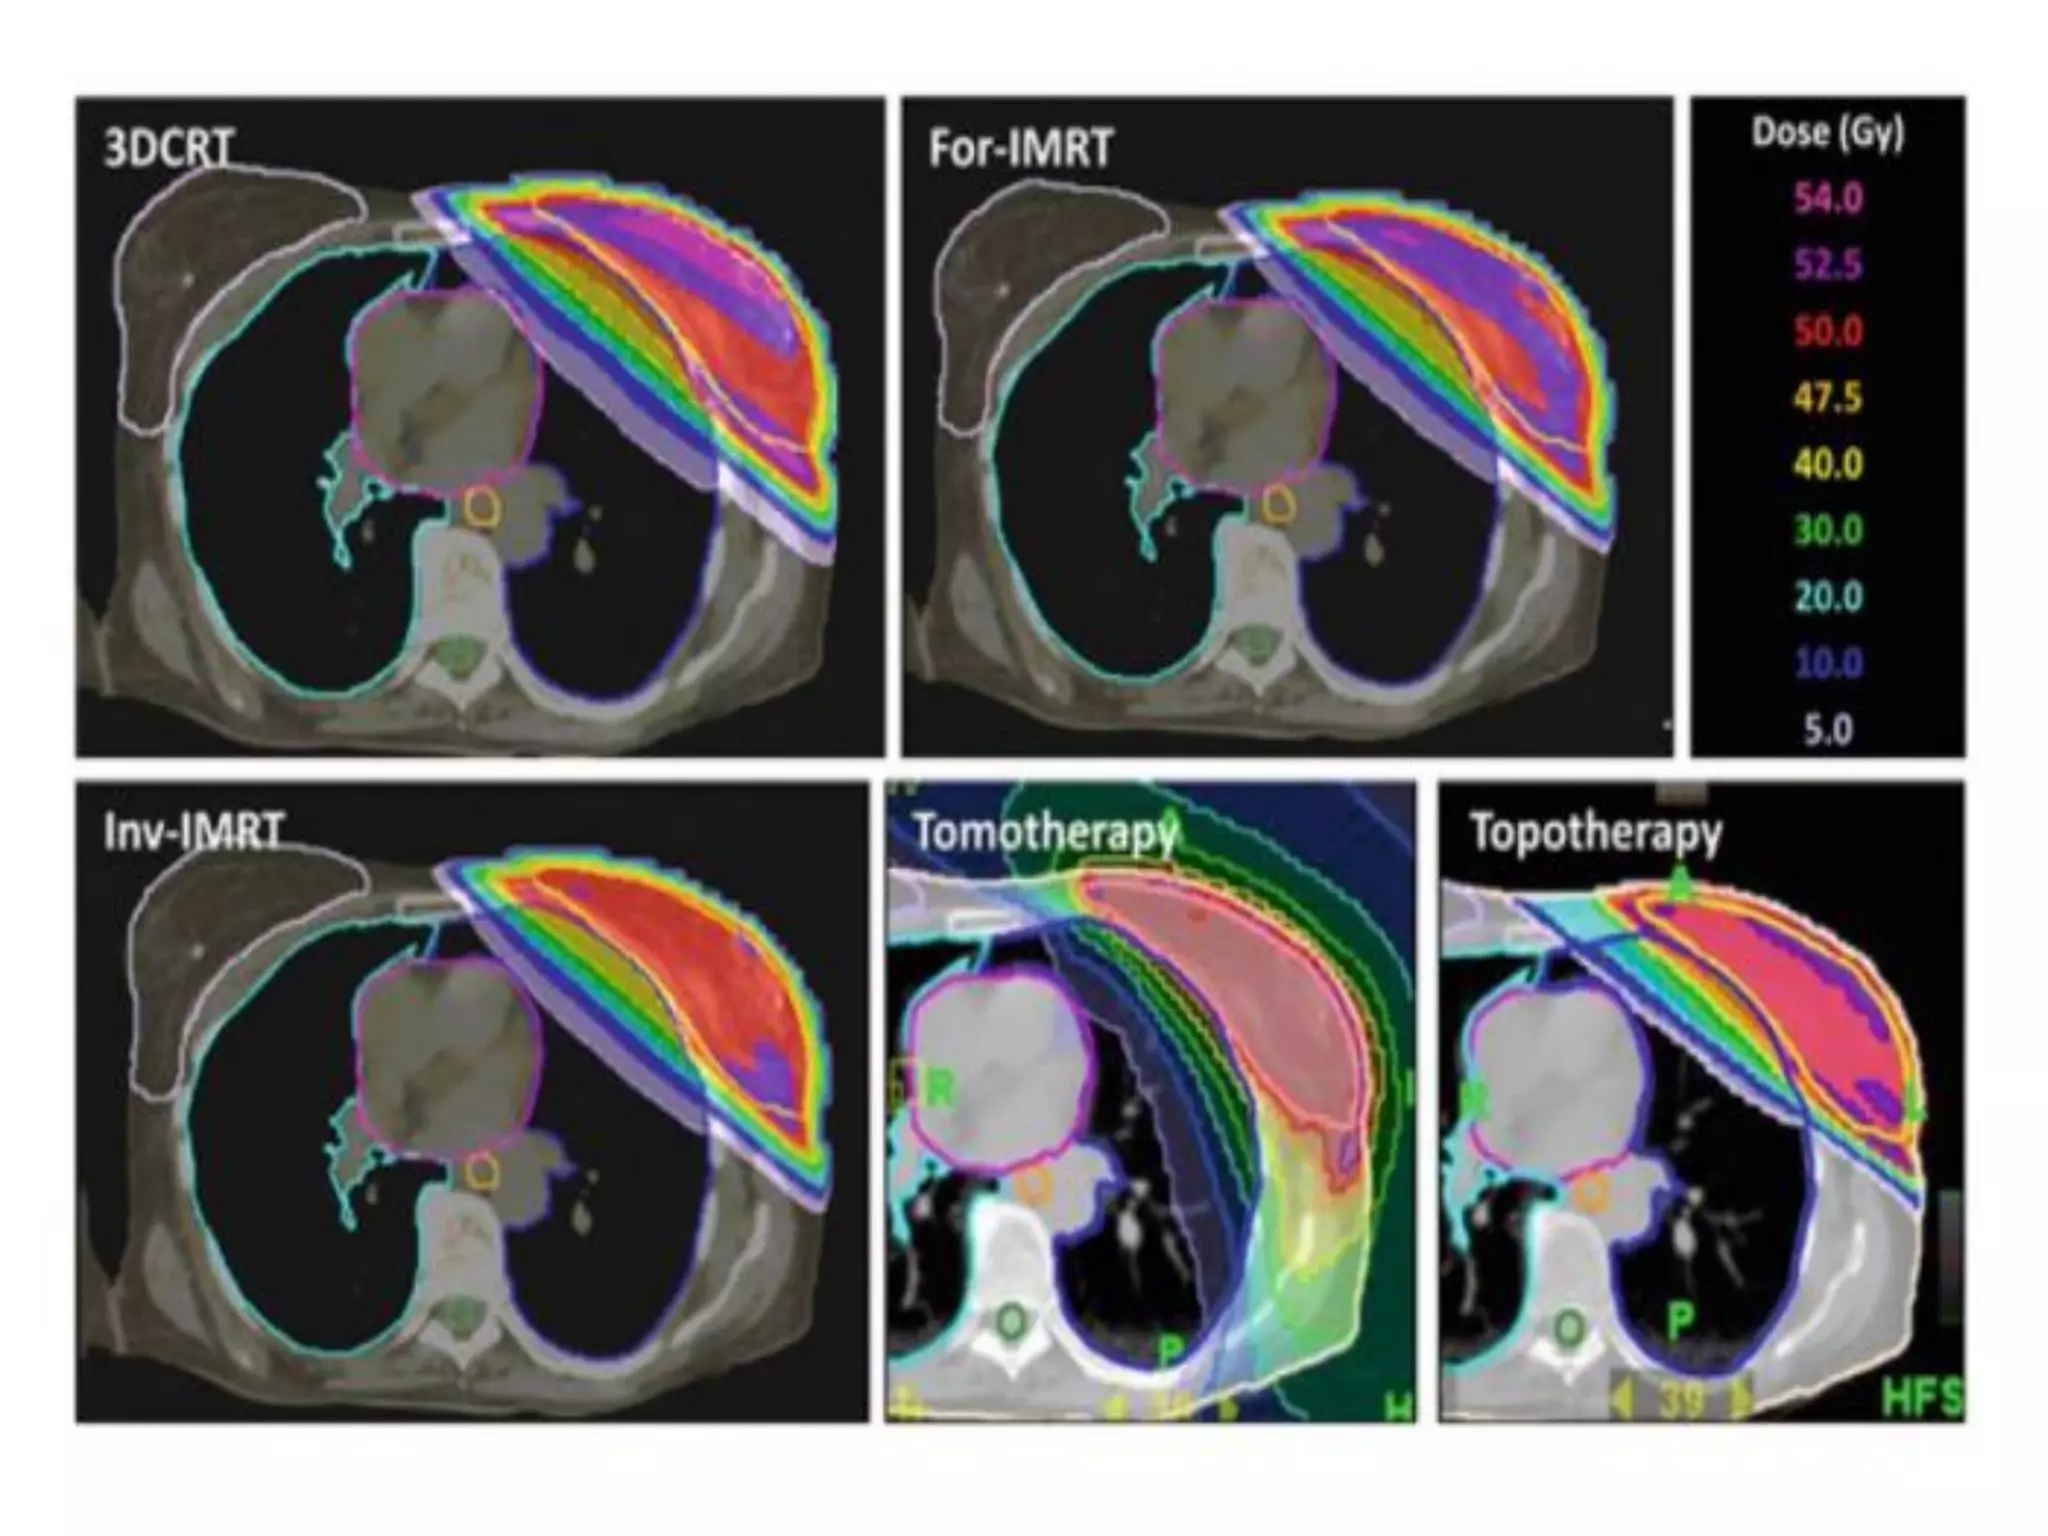

• The LINAC is used to treat all body sites, using

conventional techniques, Intensity-Modulated

Radiation Therapy (IMRT), Volumetric Modulated

Arc Therapy (VMAT), Image Guided Radiation

Therapy (IGRT), Stereotactic Radiosurgery (SRS) and

Stereotactic Body Radio Therapy (SBRT).

What is LINACused for • The linear accelerator is used to treat all parts/organs of the body. • It delivers high-energy x-rays or electrons to the region of the patient's tumor. • These treatments can be designed in such a way that they destroy the cancer cells while sparing the surrounding normal tissue. • The LINAC is used to treat all body sites, using conventional techniques, Intensity-Modulated Radiation Therapy (IMRT), Volumetric Modulated Arc Therapy (VMAT), Image Guided Radiation Therapy (IGRT), Stereotactic Radiosurgery (SRS) and Stereotactic Body Radio Therapy (SBRT).

Treatment Planning • Thegoal of treatment planning is to maximize the radiation dose to the tumor while minimizing the dose to organs at risk. • The best treatment plan for each patient is determined by a team consisting of radiation oncologists, medical physicists, medical dosimetrist, and radiation therapist, they plan the appropriate external beam radiotherapy.